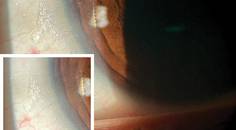

Real Talk About Eyelash Enhancements

Jason E. Compton, OD, FAAO; Mahnia Madan, OD, FAAOJason E. Compton, OD, FAAO; Mahnia Madan, OD, FAAO